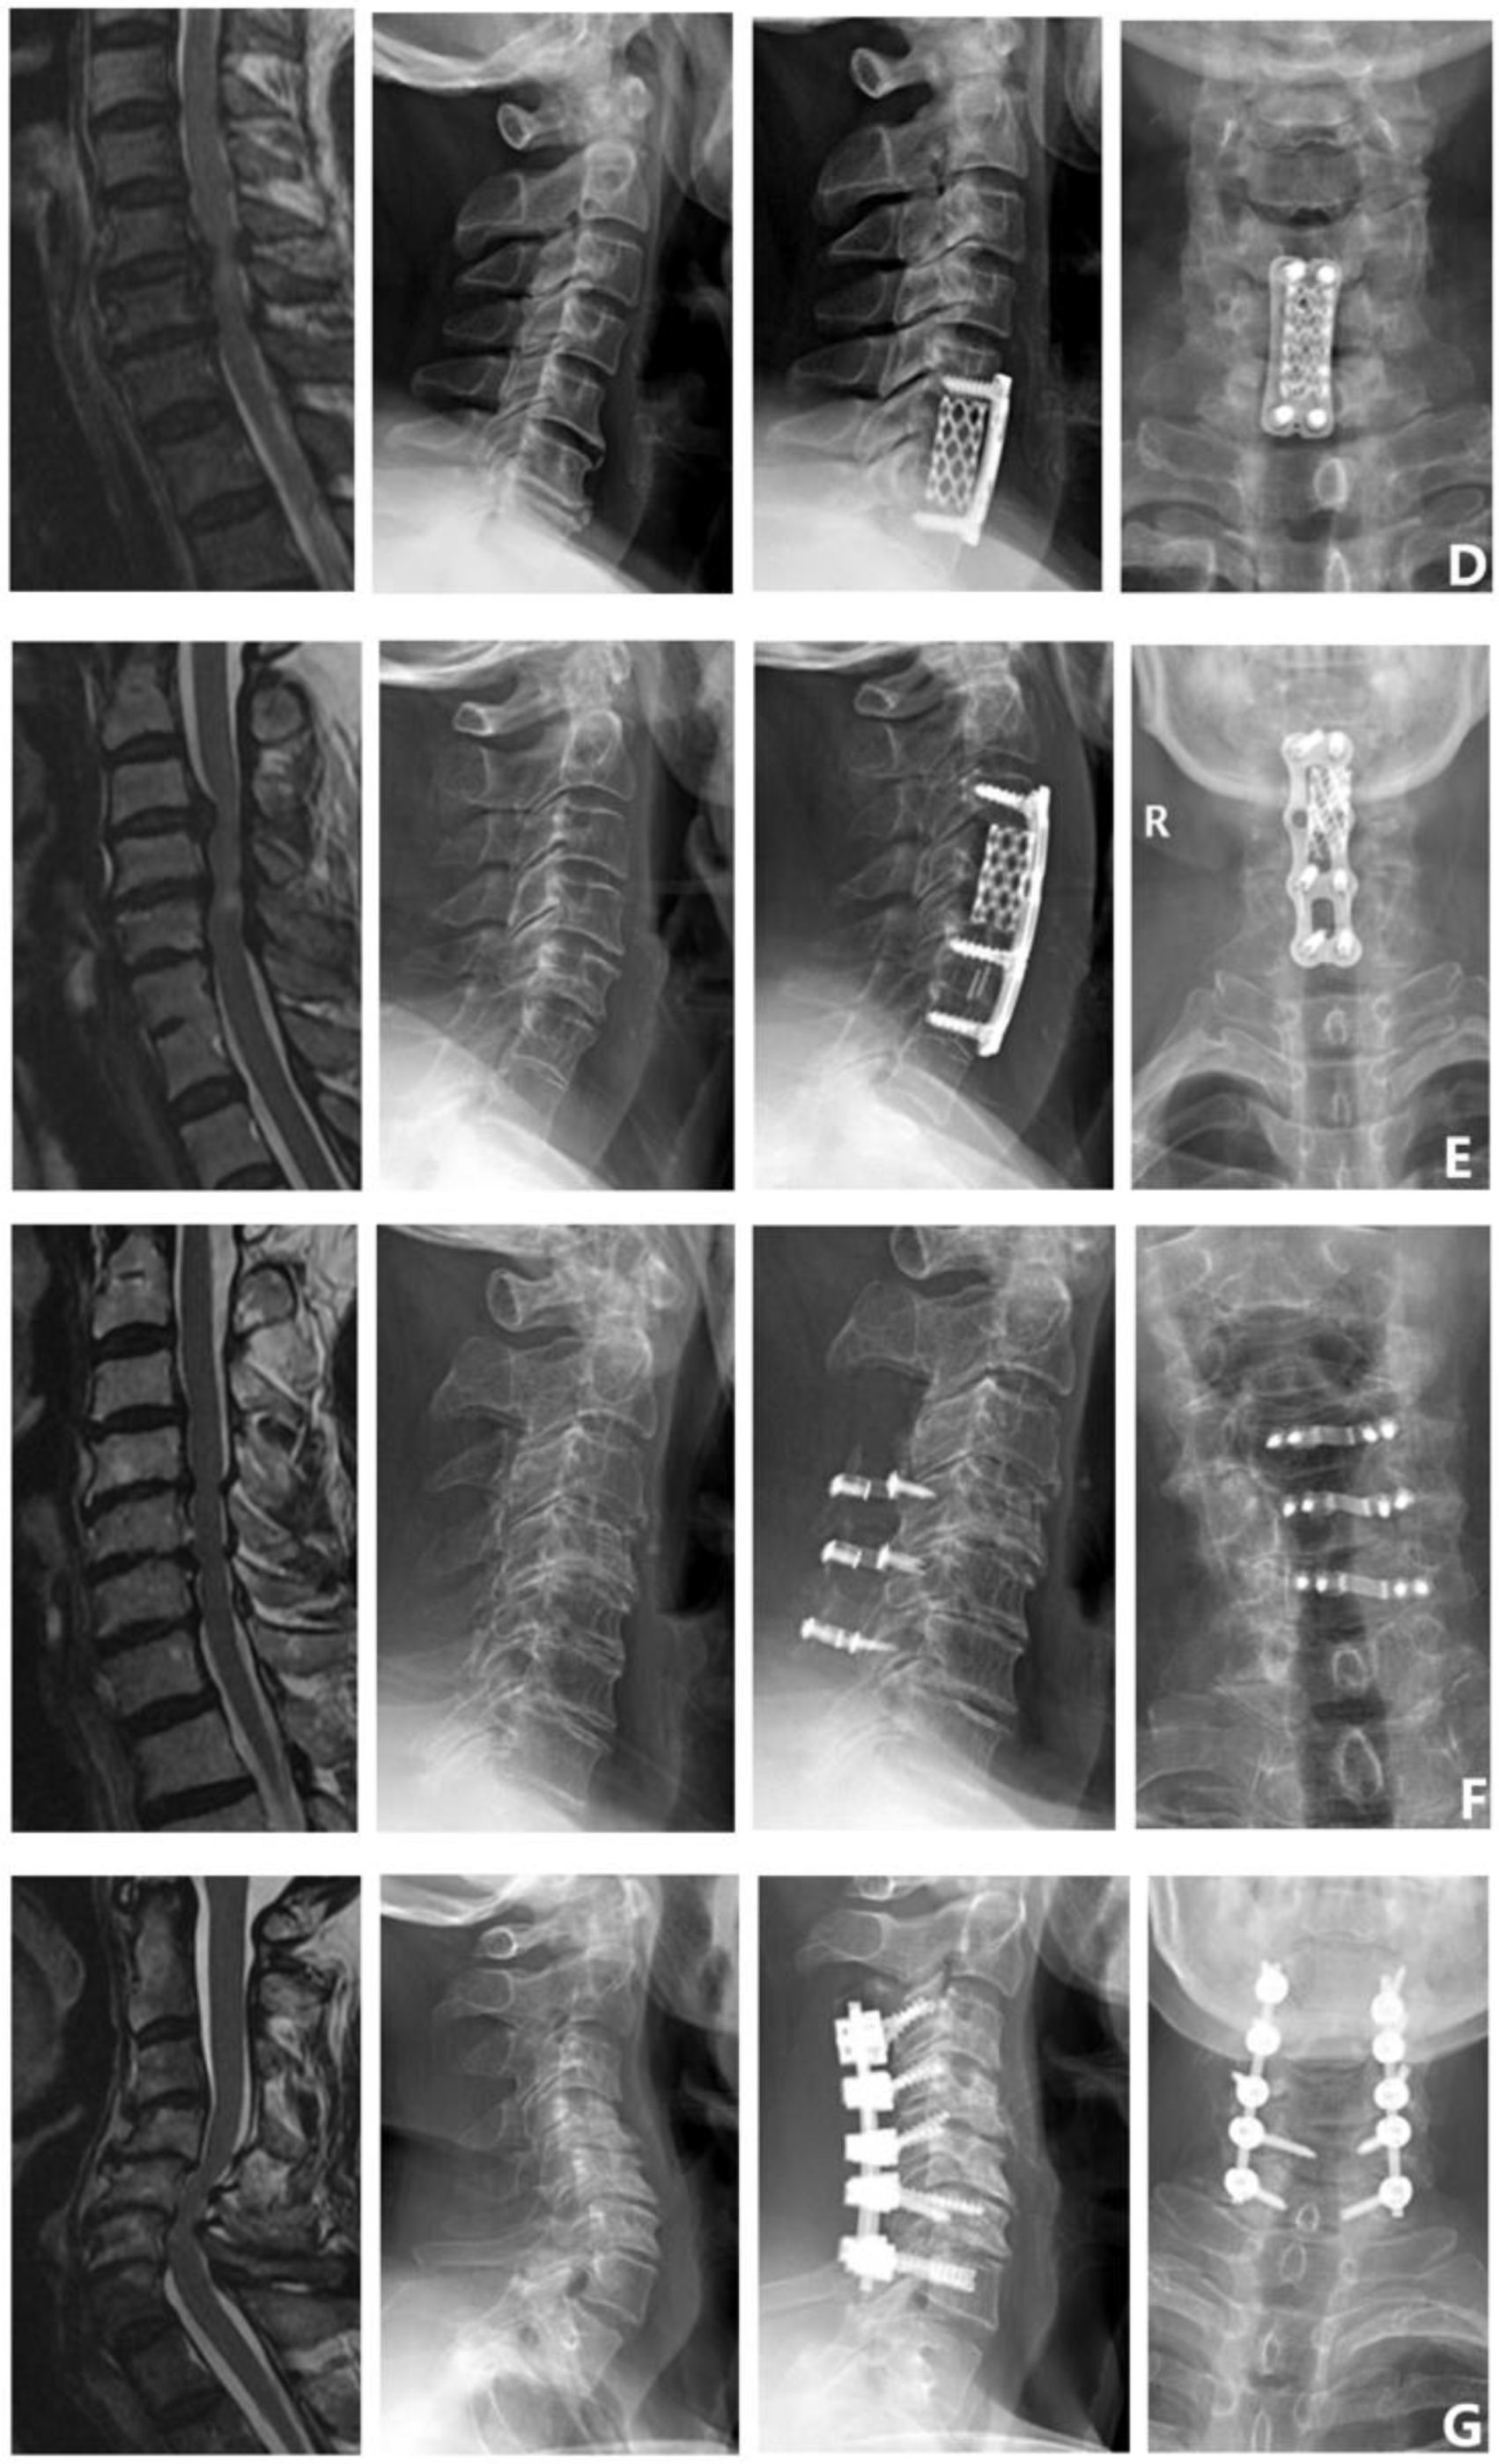

Surgical methods: ① Single-segment anterior cervical decompression and fusion (single ACDF). ② Double-segment anterior cervical decompression and fusion (double ACDF). ③ Three-segment anterior cervical decompression and fusion (three ACDF). ④ Anterior cervical corpectomy and fusion (ACCF). ⑤ Anterior cervical hybrid decompression and fusion (ACHDF). ⑥ Posterior cervical laminectomy (laminoplasty). ⑦ Posterior cervical laminectomy and fusion (laminectomy and fusion) (Figure 2).

Figure 2.

Surgical methods. (A) Single ACDF. (B) Double ACDF. (C) Three ACDF. (D) ACCF. (E) ACHDF. (F) Laminoplasty. (G) Laminectomy and fusion.